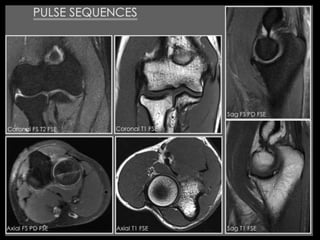

The sagittal plane is perpendicular to bicondylar plane, allowing a good

study of anterior and posterior horn of the menisci and cruciate ligaments.

The frontal (coronal) plane parallel to bicondylar

plan is systematic and can analyze the middle

segment of the meniscus and collateral ligaments.

The axial plane provides a good analysis of periarticular tissues

(muscles, tendons, nerves and vessels). They allow more precise

study of patella-femoral cartilage and the popliteal fossa.